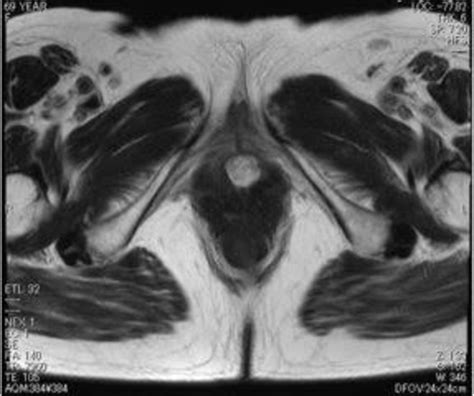

Urethral Caruncle Images: Examples

Below are some examples of urethral caruncle images that illustrate the typical appearance of these growths. These images are provided for educational purposes and should not be used for self-diagnosis. Always consult a healthcare provider for a proper diagnosis and treatment.

Urethral Caruncle Image 1 Urethral Caruncle Image 2

These images show the characteristic red, fleshy growths that are typical of urethral caruncles. The size and shape of the caruncles can vary, but they are usually small and located at the urethral opening. Urethral caruncle images can be a valuable tool in the diagnostic process, providing a visual reference for healthcare providers and patients.